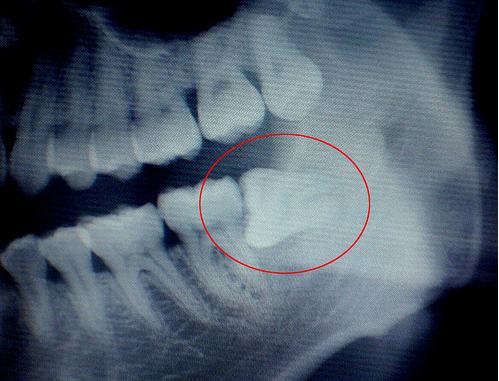

这图片是阻生智齿,也就包括横着长的智齿拔除,会比较复杂些,平常简单的拔牙就是用工具将牙齿拔掉,不用缝线,上个药就搞定啦。

如果智齿能顺利长出的话最好不过了,但有些智齿长不出来,尤其是横着的,是一项难度较大的小手术,先将黏膜切开,然后去骨....犹如剖腹产一样。拔掉后不需要镶牙,有利于身体健康,保护附近其他牙齿。